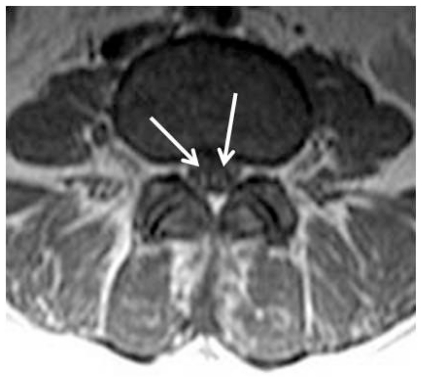

Figure 5.

39 year-old female with Guillain-Barré syndrome secondary to systemic lupus erythematosus. There are no abnormalities on the precontrast axial SE T1-weighted MR image at the level of the L4 vertebrae.

39 year-old female with Guillain-Barré syndrome secondary to systemic lupus erythematosus. The nerve roots in the conus medullaris and cauda equina are normal on the axial TSE T2-weighted MR image at the level of the L4 vertebrae (arrow).

Figure 4.